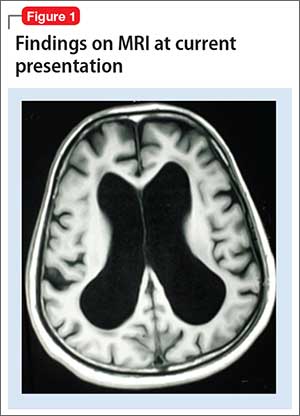

Mr. X is referred to a neurologist, based on cognitive impairment and gait disturbance, who orders an MRI scan of the brain that shows enlarged ventricles and some cortical atrophy (Figure 1). A neurosurgeon removes approximately 25 mL of CSF as a diagnostic and therapeutic intervention.